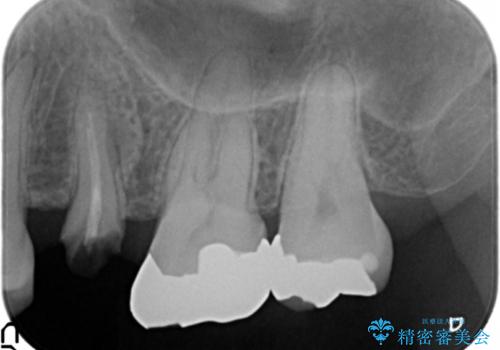

放置し崩壊した歯 セラミック治療による咬合機能回復

- 忙しくて歯科医院に通えず、ついに歯が折れてしまい治療を希望され来院されました。

虫歯を丁寧に除去したのち、なんとか歯を残せる見通しがたったので根管治療を行いセラミック補綴を行いました。